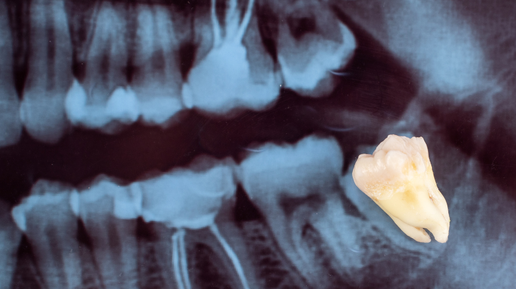

Зубы мудрости, «восьмерки», третьи моляры – наследство, оставленное нам далеким предком с широкой челюстью и мощными зубами. Считается, что последние в ряду зубы – рудименты. То есть элементы, которые в процессе эволюции из-за изменений в нашем рационе стали ненужными. Грубая и жесткая пища прежних веков, требующая усилий и перемалывания, заменилась на нашем столе на более мягкую, кулинарно обработанную. Когда нагрузка снизилась, то и челюсть современного человека уменьшилась. А вот зубы пока остались...

Зубы мудрости. Лечить или удалять?

"Это зуб мудрости и нет смысла его лечить". Именно эту фразу обычно мы слышим в кресле стоматолога. Но почему многие стоматологи так категорично относятся к данной группе зубов и "не хотят" лечить зубы мудрости? Ещё со времен муниципальной стоматологической поликлиники, когда не было разницы где лечить зубы, так как материалы практически не отличались, если пациент приходил к стоматологу-терапевту (далее терапевт) с жалобами на боли в зубе мудрости, то врач отправлял его к хирургу. Почему? Давайте разбираться...